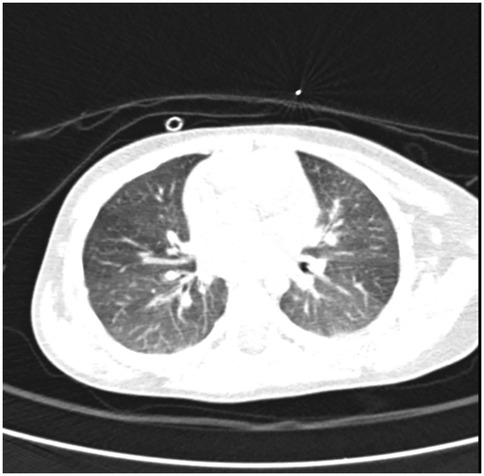

Heiner syndrome, although rare in pediatric practice, can cause cough, wheezing and only in rare cases hemoptysis. Heiner syndrome should be considered in any child presenting these respiratory symptoms and radiological evidence of alveolar infiltrates, especially when accompanied by signs of food allergy-most notably cow's milk protein allergy, although other foods seem to be involved. The use of probiotics should be evaluated with caution in these children. We report a case of a 1-year-and-6-month-old female patient who presented at the Pneumology Clinic with a one-day history of blood-tinged sputum. Although the patient had a known history of cow's milk protein allergy and well-controlled asthma, the occurrence of hemoptysis, even though in small quantities, raised concerns to the family. A second episode of hemoptysis appears when she received egg and probiotic. After correlating the patient's medical history with clinical, laboratory, and imaging findings, a diagnosis of Heiner syndrome was established. The patient received emergency treatment followed by bronchodilators, corticosteroid therapy, and restricted diet for cow's milk protein and egg. The patient's condition improved immediately after treatment and remained stable at the 5-month follow-up. The differential diagnosis with idiopathic pulmonary hemosiderosis must not be overlooked, due to its more severe clinical course and higher risk of complications.